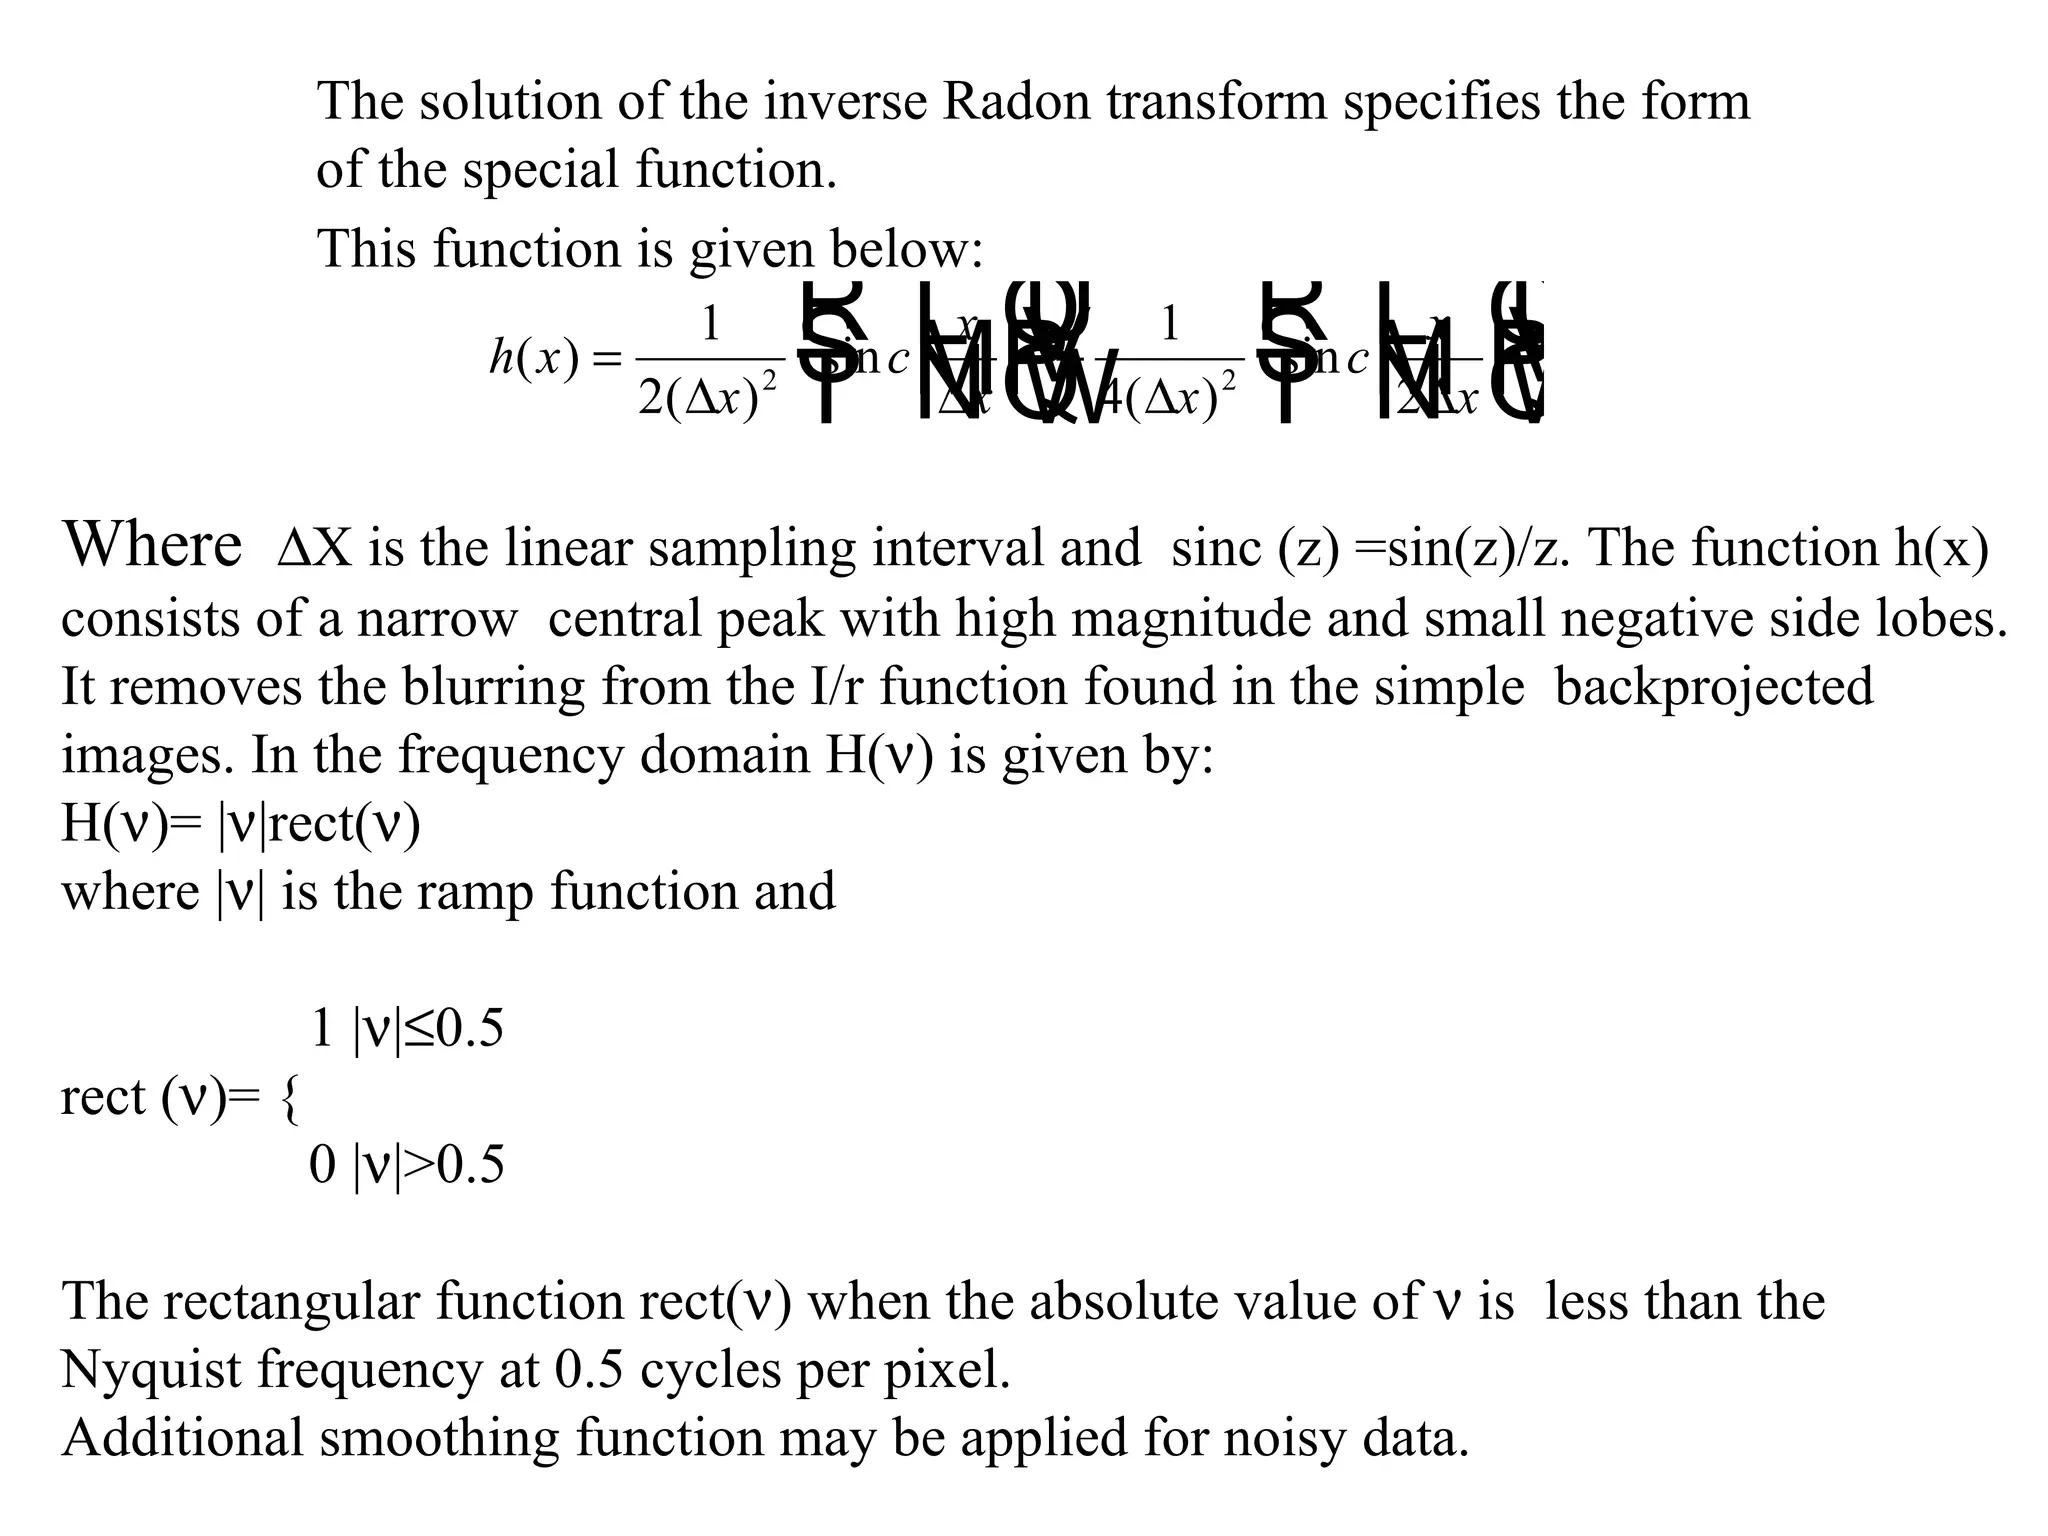

The document discusses various medical imaging modalities including x-rays, computed tomography (CT), and digital mammography. It describes the basic principles and historical development of these technologies, how images are formed, and what types of anatomical features and abnormalities they can detect. Key advances include the development of digital systems that allow image manipulation and remote consultation. While promising, digital mammography still faces challenges around resolution and cost.